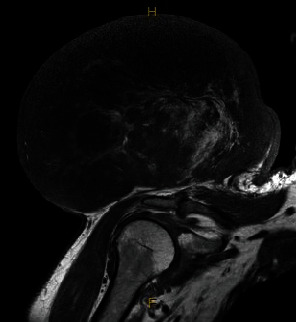

This study examines a unique case of a 61-year-old male with a 5-year history of a progressively growing mass above his right shoulder, diagnosed as a dedifferentiated pleomorphic liposarcoma. Using computerized tomography-guided core needle biopsy, the tumour was identified as intermediate to high grade. Surgical removal required preoperative radiotherapy to reduce the size of the tumour. Several unique characteristics set apart this particular case of liposarcoma: its substantial size, its unpredictable growth pattern, its absence of metastasis, and notably, its prolonged period of being untreated. This case report outlines the clinical background, diagnostic procedures, and treatment modalities employed in managing this condition, emphasizing a localized dual therapy approach combining radiotherapy and surgery. Emphasis is placed on distinguishing liposarcoma from lipoblastoma, a benign adipocyte tumour, to facilitate accurate diagnosis and appropriate treatment selection. The positive result achieved in this case could provide valuable insights for the future treatment and management of similarly sized aggressive tumours.